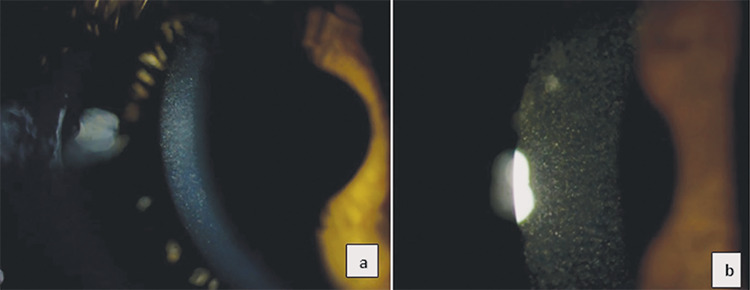

Cystinosis is a rare autosomal recessive lysosomal storage disease associated with high mortality and morbidity rates. The most distinctive ocular manifestations of cystinosis are photophobia, tearing, and blurred vision. Herein, we assessed the ocular involvement of four patients from two families diagnosed with infantile nephropathic cystinosis using optical coherence tomography (OCT) and in vivo confocal microscopy (IVCM). Anterior segment OCT demonstrated multiple hyperreflective punctate deposits, and IVCM revealed needle-shaped bright crystal deposits in the corneal stroma in all patients. Three patients also had crystal deposits in the epithelium, where epithelial cell disruption was observed. Crystal deposits around the subepithelial nerve plexus were noted in some sections. In one patient, round and needle-shaped bright deposits along with inflammatory cells were observed in the limbal region of the conjunctiva. Infrared fundus images of two female siblings revealed hyperreflective crystal-like deposits around the optic disc, macula, and peripheral retina, and enhanced depth imaging OCT showed accumulation of crystals in all layers of the retina.